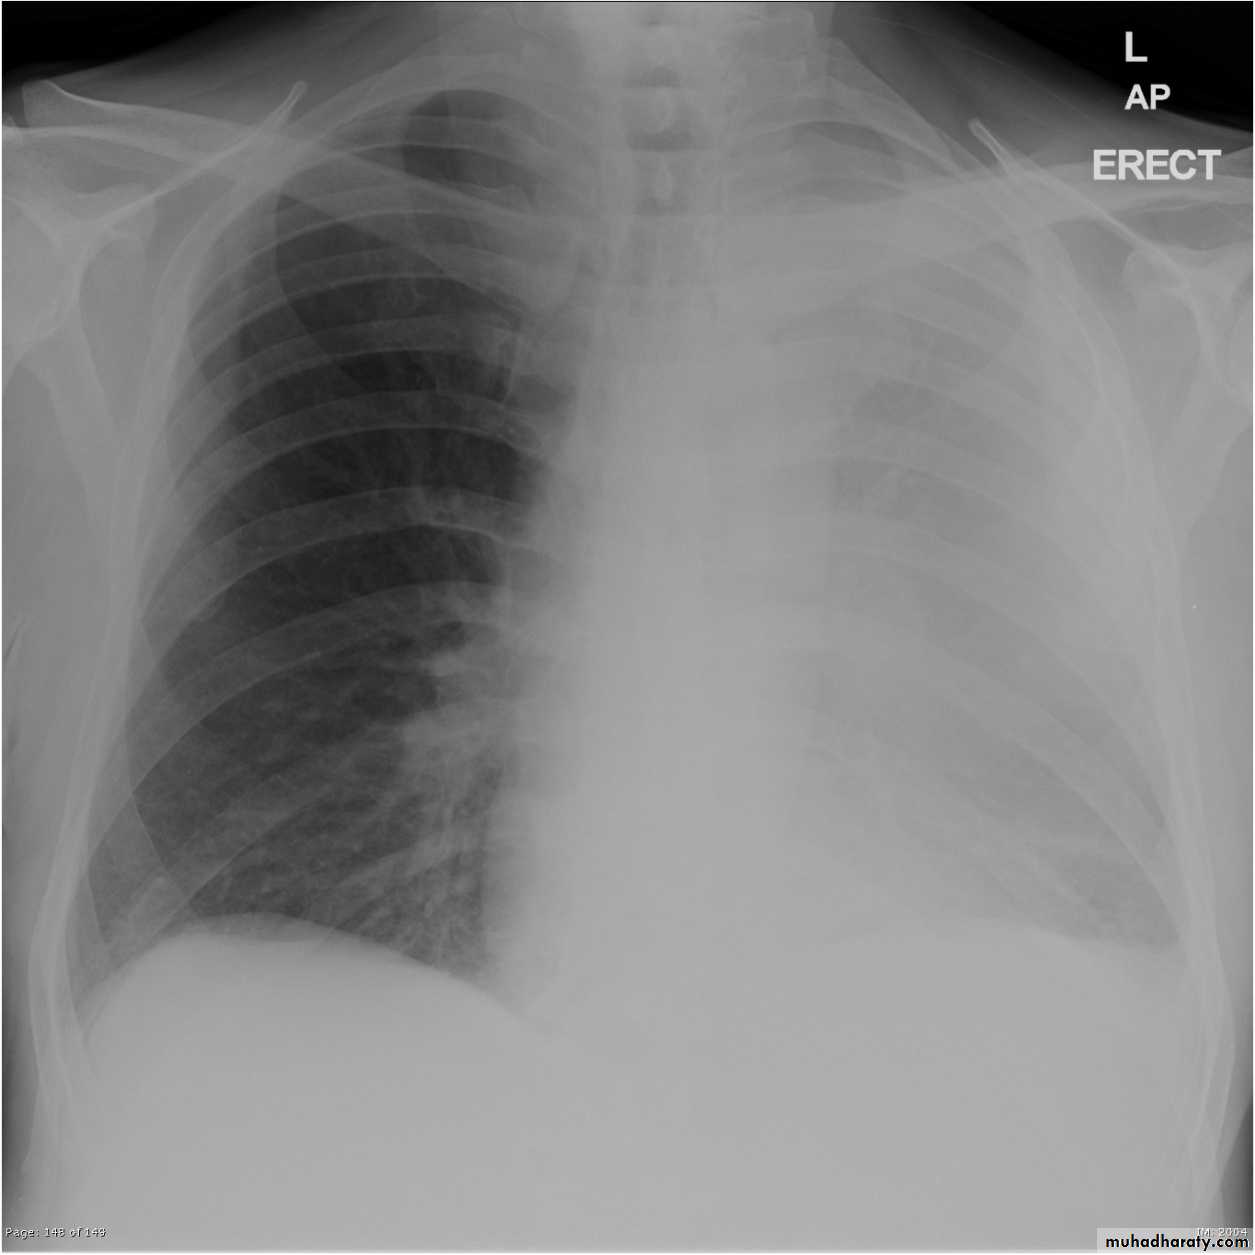

Left lower lobe collapse has distinctive features, and can be readily identified on frontal chest radiographs, provided attention is paid to the normal cardiomediastinal contours. The shadow cast by the heart does however make it harder to see than the right lower lobe collapse

Radiographic features

Left lower lobe collapseis readily identified in a well penetrated film of a patient with normal sized heart, but can be challenging in the typical patient with collapse, namely unwell patients, with portable (AP) often under-penetrated films, often with concomitant cardiomegaly. Features to be observed include :

triangular opacity in the posteromedial aspect of the left lung

edge of collapsed lung may create a 'double cardiac contour'

left hilum will be depressed

loss of the normal left hemidaphgragmatic outline

loss of the outline of the descending aorta